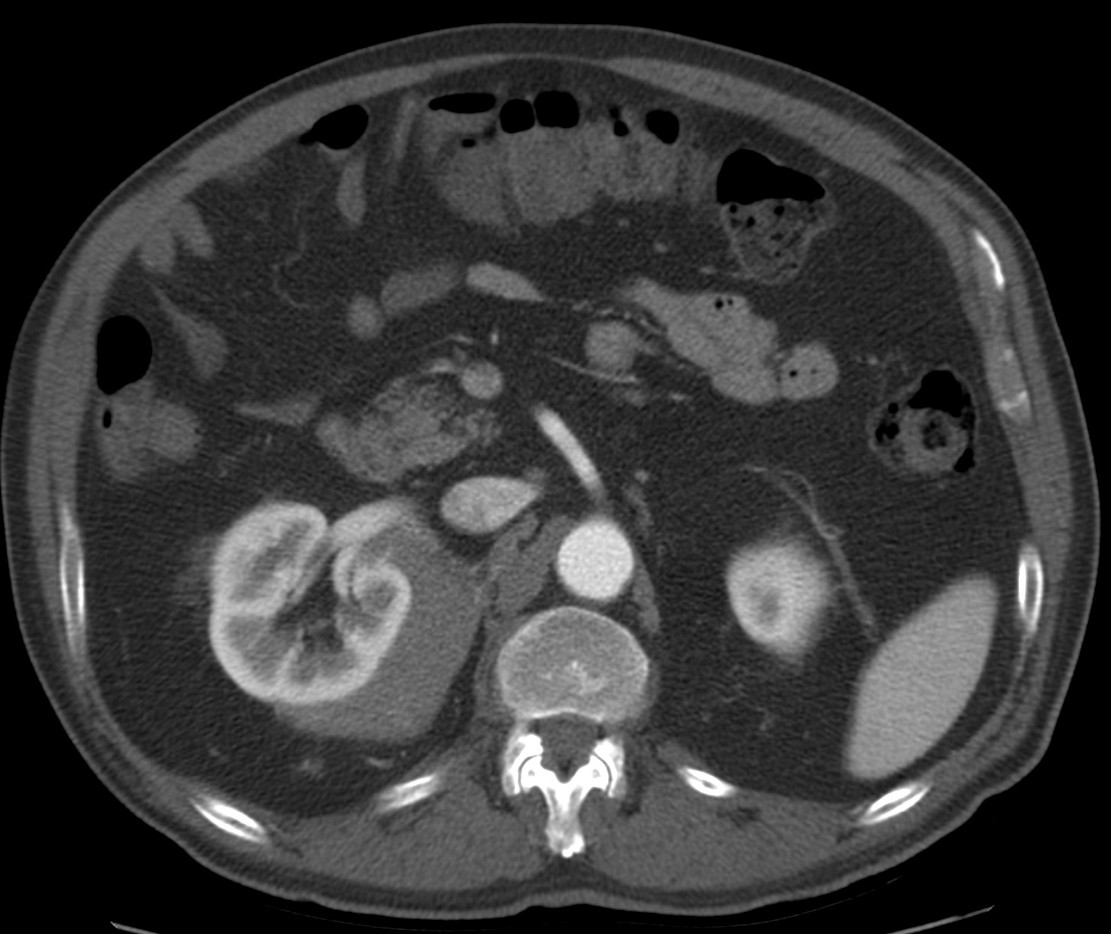

CASO 1: Paciente de 58 años que se realiza TC de abdomen tras historia de dolor abdominal y hematuria microscópica. Refiere pérdida de peso en las últimas semanas.

Estamos ante una afectación bilateral del espacio perirrenal, más evidente en el lado derecho, por masas de densidad de partes blandas en un paciente con numerosas adenopatías retroperitoneales. Estaría indicado realizar una biopsia, ya que el diagnóstico principal orienta hacia un síndrome linfoproliferativo, espcialmente linfoma no Hodgkin tipo B.